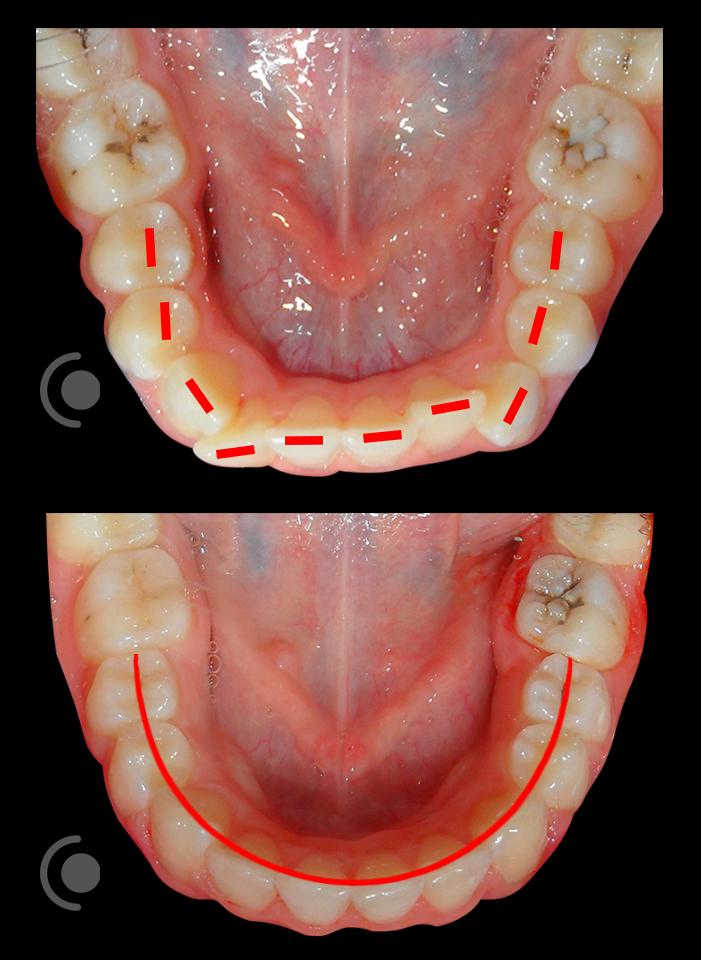

O našoj kvaliteti najbolje govore naši rezultati!

Centar za ortodonciju Petra Džapo